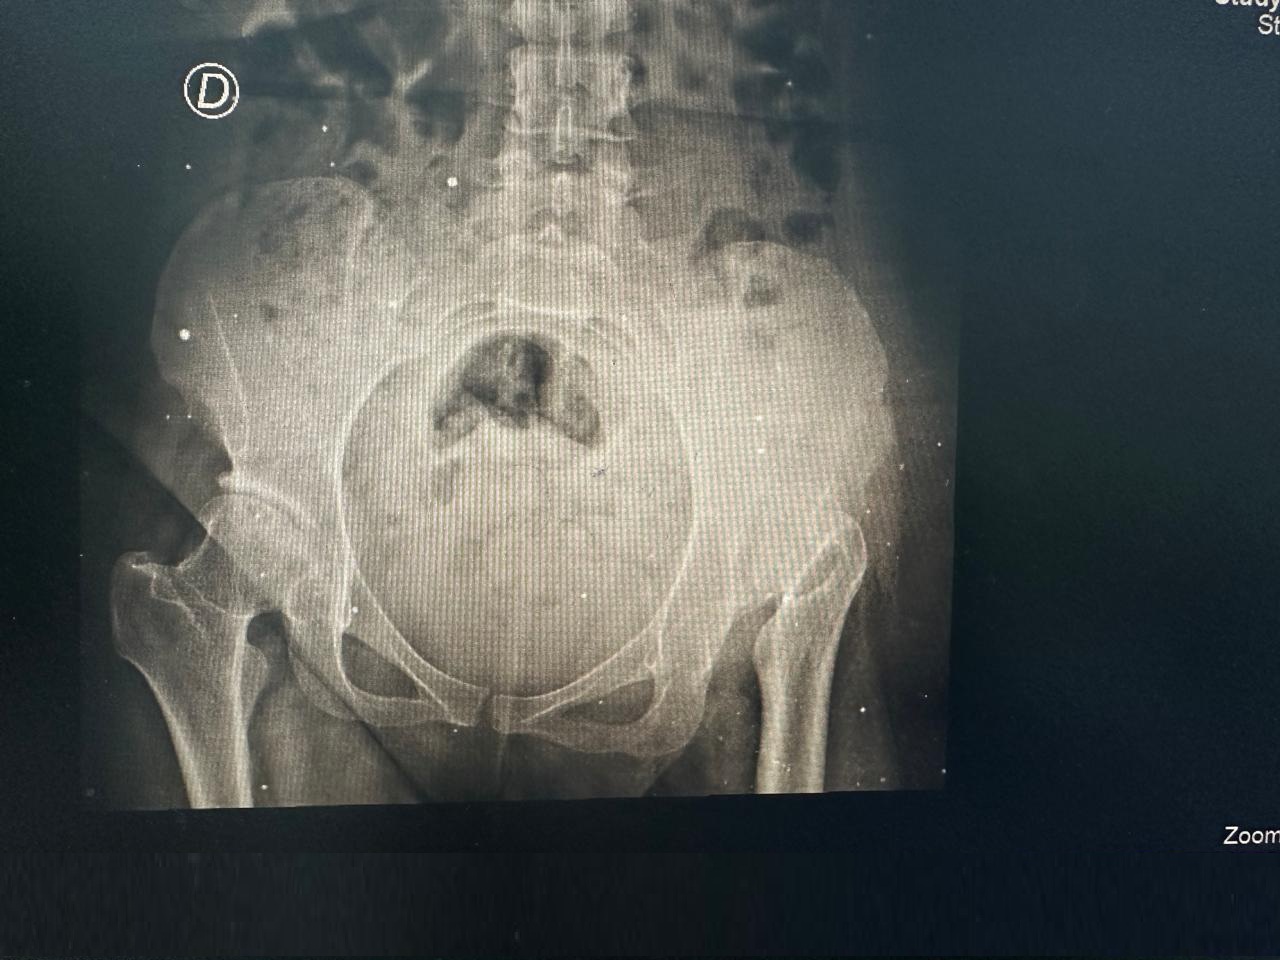

Después Radiografía postoperatoria de reemplazo total de cadera derecha exitoso - Dra. Ana Luz Bernabe

Reemplazo Articular

Artroplastia Total

de Cadera Derecha

• Perfil del Paciente: Femenino, 29 años. Cuadro de dolor severo de larga evolución.

• Diagnóstico: Limitación funcional severa para la marcha y actividades de la vida diaria.

• Procedimiento: Reemplazo total de cadera izquierda.

• Evolución (3 años): Reintegración total a sus actividades con excelente estabilidad y ausencia de dolor.